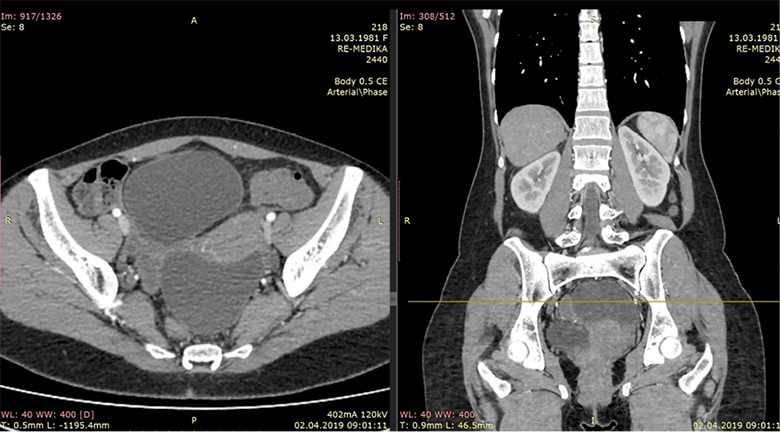

An CT scan of the abdomen was performed and were found two cystic liver formations, also a cystic formation was verified in the pelvis. The native series of the abdominal CT have shown a segment II and IV hepatic per-magna cystic formations with dimensions: No I: 80×60×74 mm (Figure 1) and No. II: 70×60×58 mm (Figure 2). The changes are with a pericystic reaction of a hypodense character. The formation in the second hepatic segment had a visible mass effect on the stomach. In post contrast series, cystic liver formations were shown as hypodense, hypovascular structures with a clearly expressed contrast accumulation in the cystic membrane and with a demarcation of the pericystic reaction. Per magna cystic formation with hypodense character was also detected at the level of the small pelvis, retrouterine, in the Douglas space, with dimensions of 93×90×62 mm (Figure 3). The cyst has a clearly expressed mass effect on surrounding organ structures. Utter in the AVF pressed to the left. The liver cystic formations were with characteristics of Ehcinococcal cyst but with no serological verification.

Figure 1. Liver segmet II permagna cystic formation

Figure 2. Segment IV hepatic cystic formation

Figure 3. Hypodense cystic formation in small pelvis